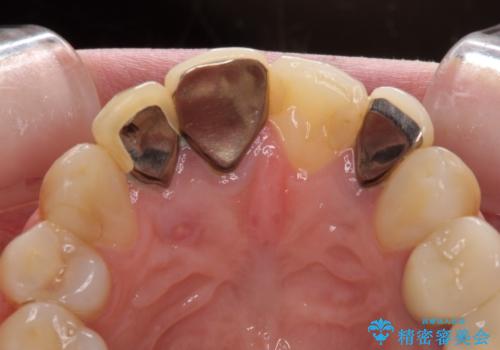

更に、土台やフレームの金属色により、歯肉ラインが黒ずんでしまっていました。

必要な歯には根管治療を行い、金属を使わない土台を植立した上で、オールセラミッククラウンにて補綴することとしました。